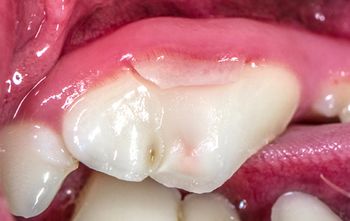

What approach would you take to fix this pups tooth and provide a solution for the long term?